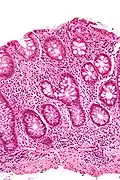

Colonic crypts

Colonic crypts (intestinal glands) within four tissue sections. In panel A, the bar shows 100 µm and allows an estimate of the frequency of crypts in the colonic epithelium. Panel B includes three crypts in cross-section, each with one segment deficient for CCOI expression and at least one crypt, on the right side, undergoing fission into two crypts. Panel C shows, on the left side, a crypt fissioning into two crypts. Panel D shows typical small clusters of two and three CCOI deficient crypts (the bar shows 50 µm). The images were made from original photomicrographs, but panels A, B and D were also included in an article[7]

The intestinal glands in the colon are often referred to as colonic crypts. The epithelial inner surface of the colon is punctuated by invaginations, the colonic crypts. The colon crypts are shaped like microscopic thick-walled test tubes with a central hole down the length of the tube (the crypt lumen). Four tissue sections are shown here, two (A and B) cut across the long axes of the crypts and two (C and D) cut parallel to the long axes.

In these images the cells have been stained to show a brown-orange color if the cells produce a mitochondrial protein called cytochrome c oxidase subunit I (CCOI or COX-1). The nuclei of the cells (located at the outer edges of the cells lining the walls of the crypts) are stained blue-gray with haematoxylin. As seen in panels C and D, crypts are about 75 to about 110 cells long. The average crypt circumference is 23 cells.[8] From the images, an average is shown to be about 1,725 to 2530 cells per colonic crypt. Another measure was attained giving a range of 1500 to 4900 cells per colonic crypt.[9] Cells are produced at the crypt base and migrate upward along the crypt axis before being shed into the colonic lumen days later.[8] There are 5 to 6 stem cells at the bases of the crypts.[8]

As estimated from the image in panel A, there are about 100 colonic crypts per square millimeter of the colonic epithelium.[10] The length of the human colon is, on average 160.5 cm (measured from the bottom of the cecum to the colorectal junction) with a range of 80 cm to 313 cm.[11] The average inner circumference of the colon is 6.2 cm.[10] Thus, the inner surface epithelial area of the human colon has an area, on average, of about 995 cm2, which includes 9,950,000 (close to 10 million) crypts.

In the four tissue sections shown here, many of the intestinal glands have cells with a mitochondrial DNA mutation in the CCOI gene and appear mostly white, with their main color being the blue-gray staining of the nuclei. As seen in panel B, a portion of the stem cells of three crypts appear to have a mutation in CCOI, so that 40% to 50% of the cells arising from those stem cells form a white segment in the cross cut area.

Overall, the percentage of crypts deficient for CCOI is less than 1% before age 40, but then increases linearly with age.[7] Colonic crypts deficient for CCOI reaches, on average, 18% in women and 23% in men, by 80–84 years of age.[7]

Crypts of the colon can reproduce by fission, as seen in panel C, where a crypt is dividing to form two crypts, and in panel B where at least one crypt appears to be fissioning. Most crypts deficient in CCOI are in clusters of crypts (clones of crypts) with two or more CCOI-deficient crypts adjacent to each other (see panel D).[7]